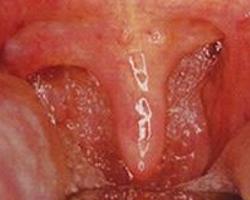

萎缩性咽炎常继发于萎缩性鼻炎,病因不明。萎缩性咽炎是咽粘膜与腺体的一种退行性炎性病变。成年人多见。常与萎缩性鼻炎同时存在。多系萎缩性鼻炎向后蔓延所致。萎缩性咽炎常继萎缩性鼻炎而起,病因不明,临床上也很少见。主要病理变化为咽部腺体和粘膜萎缩。[1]